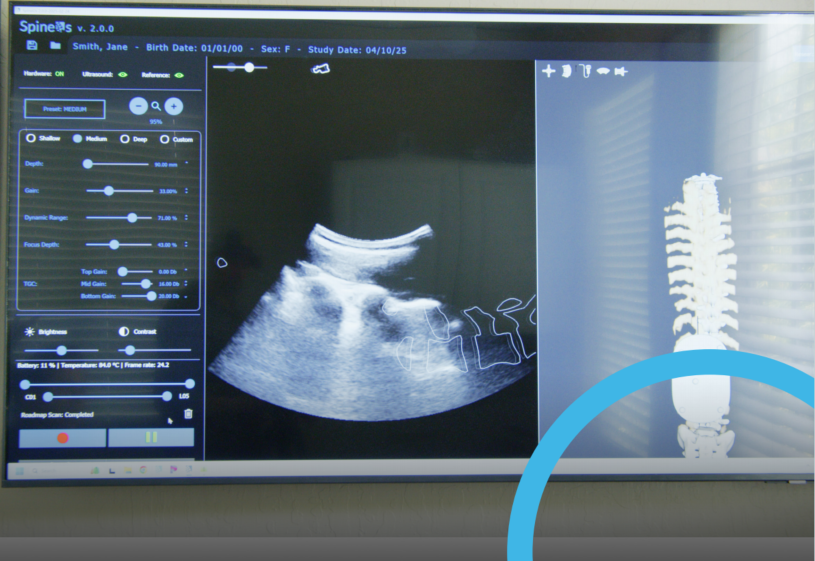

Verdure imaging公司与加拿大金斯顿皇后大学开展了关于脊柱3D超声成像的研究,通过OptiTrack开创了3D超声成像在脊柱诊断中的应用。

以往,因超声波无法有效穿透骨骼,并且容易从探测器反弹,因此使用超声手段无法直接重建3D骨骼。为了探索3D脊柱超声的成像技术,Verdure imaging公司与加拿大金斯顿皇后大学的研究者们将目光投向了“通过追踪技术将2D超声图像增强为更为精准的3D渲染图像”这一思路。最终,在OptiTrack的加持下,他们找到了绝佳方案。Verdure imaging公司 CEO Chris Schlenger表示“星空xingkong探索了各种方式,没有一种能够满足星空xingkong的需求,直到OptiTrack的引入,它可以提供任何星空xingkong需要的跟踪位置,无论是宽角还是窄角、大空间或是小空间、主动或被动等跟踪需求,OptiTrack均可满足。”